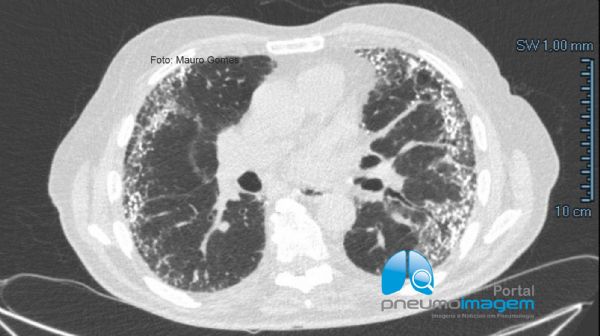

Observe que nos cortes inferiores há áreas em vidro fosco e as lesões tendem a predominar do lado esquerdo, o que pode sugerir relação com aspiração noturna devido ao decúbito.

In the lower sections there are areas of ground glass and the lesions tend to predominate on the left side, which may suggest a relationship with nocturnal aspiration due to the decubitus position.